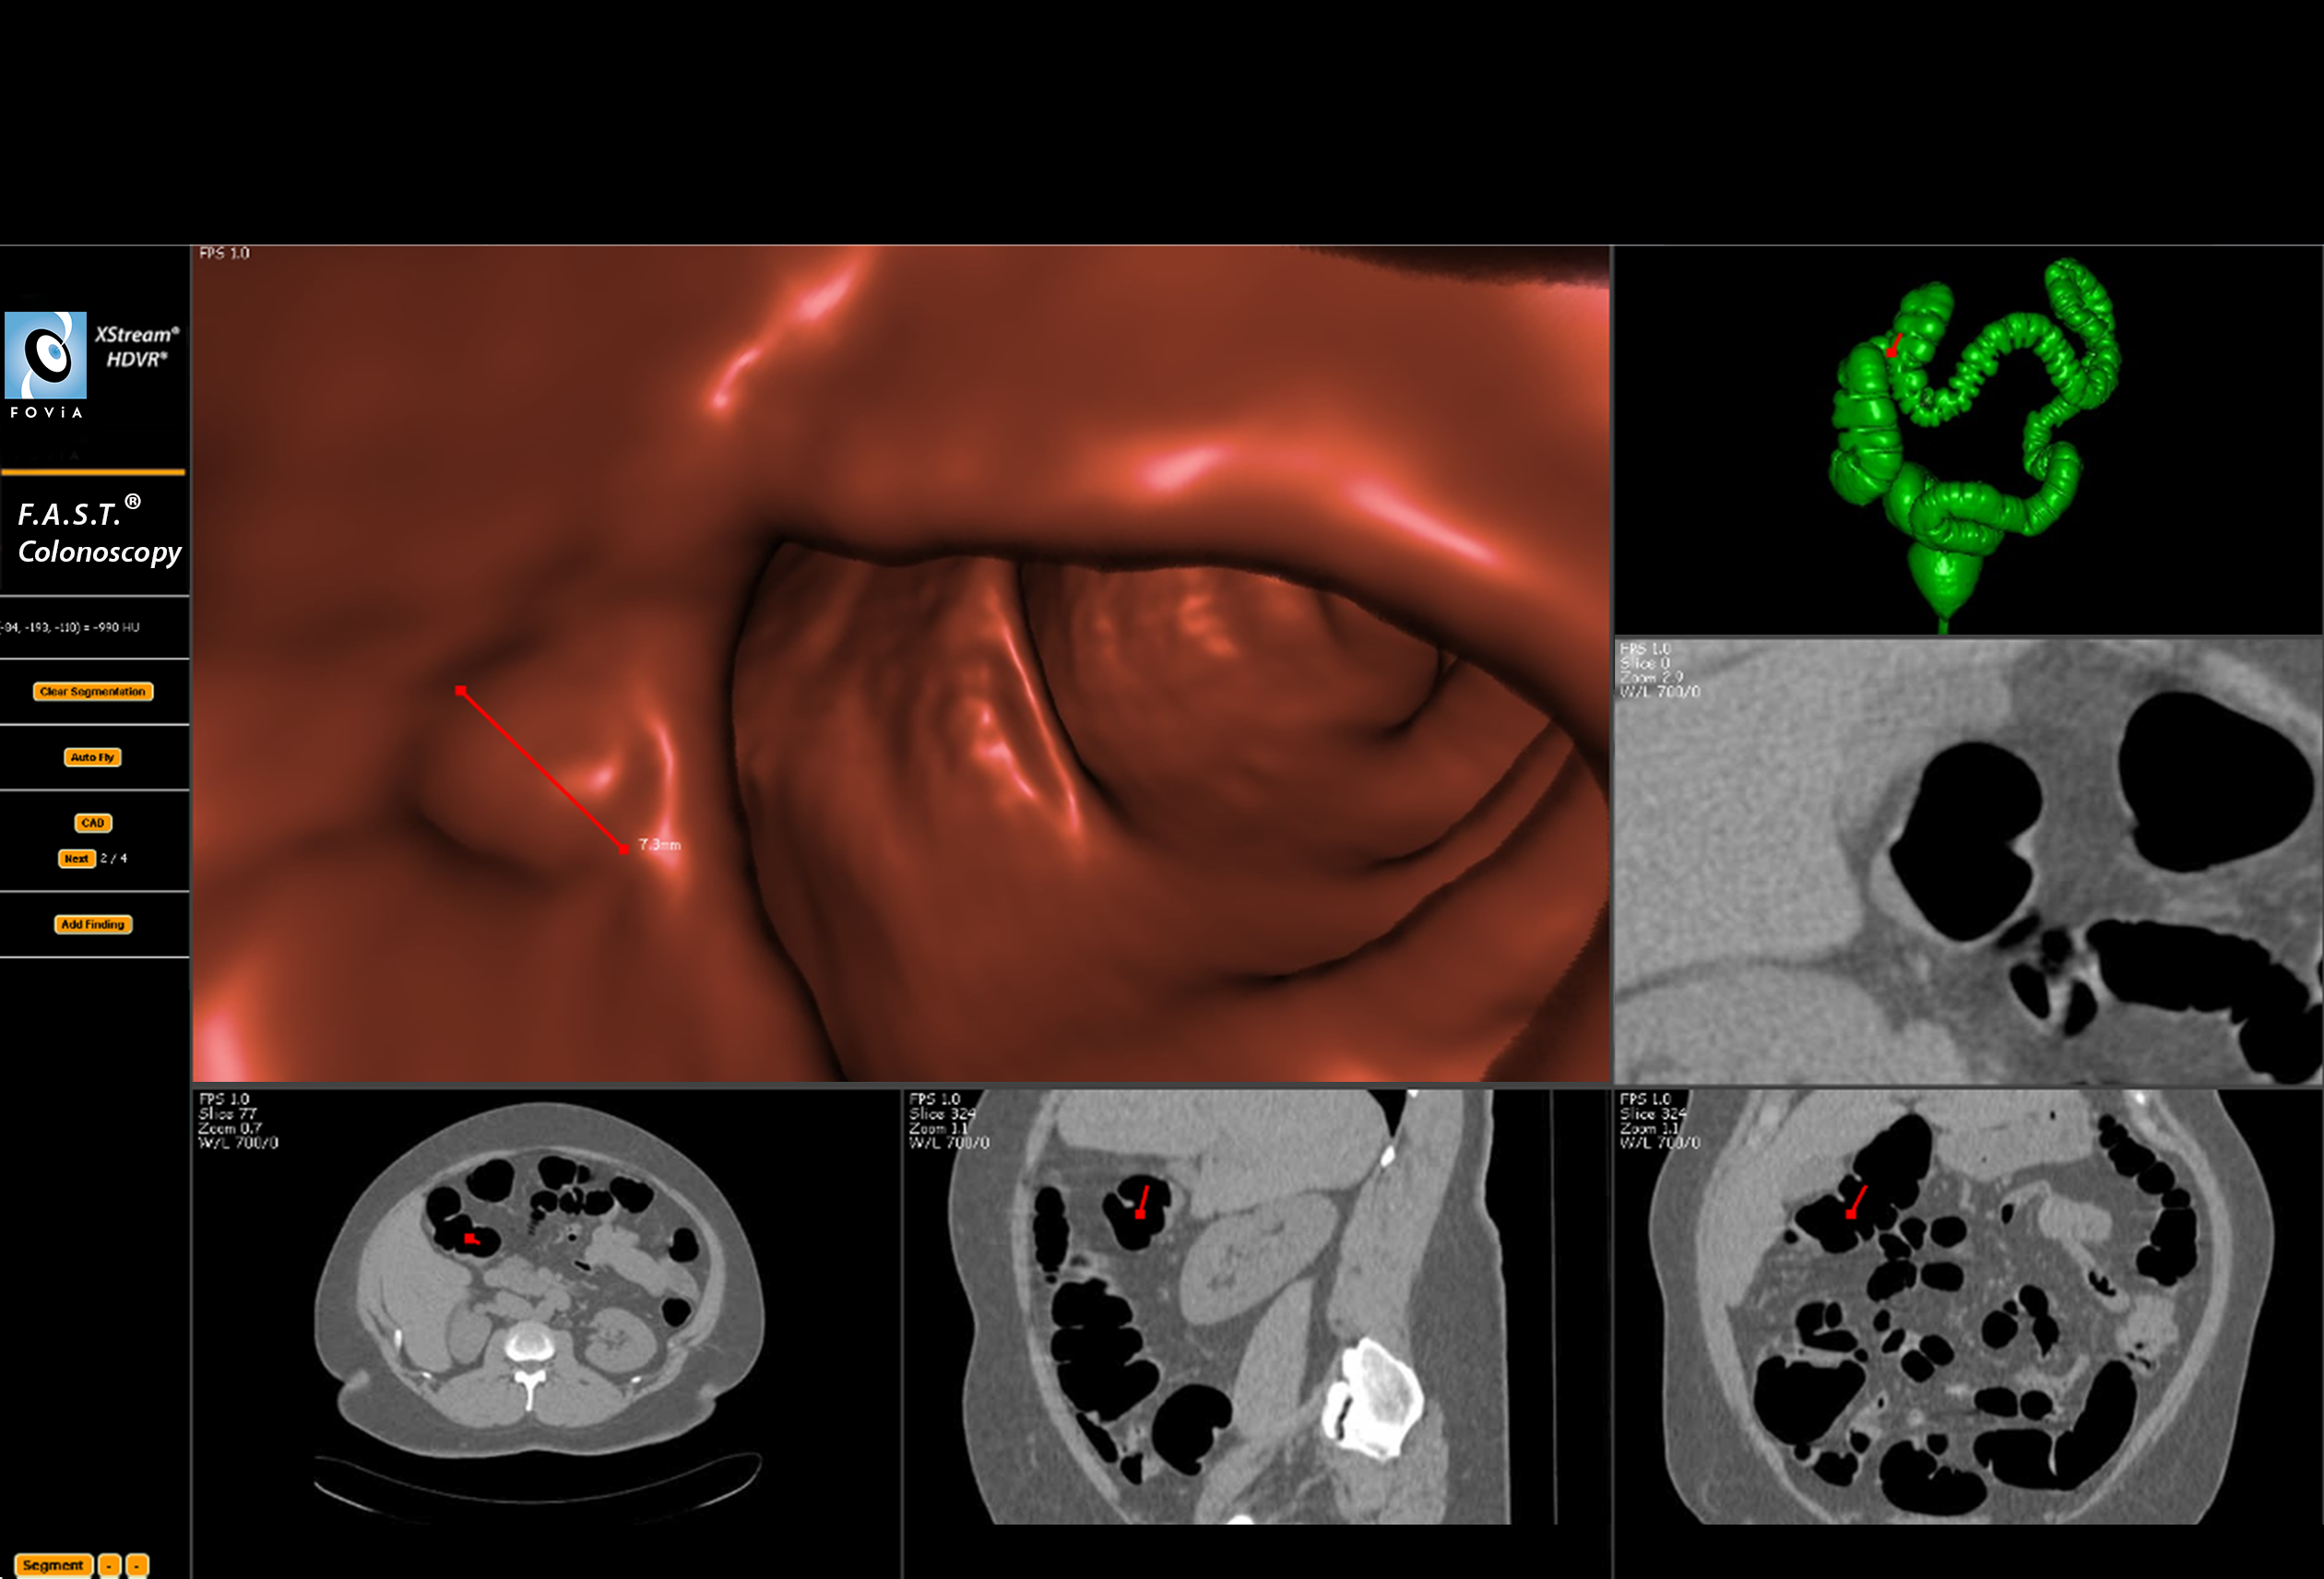

F.A.S.T. Colonoscopy Workflow

F.A.S.T. Colonoscopy Workflow